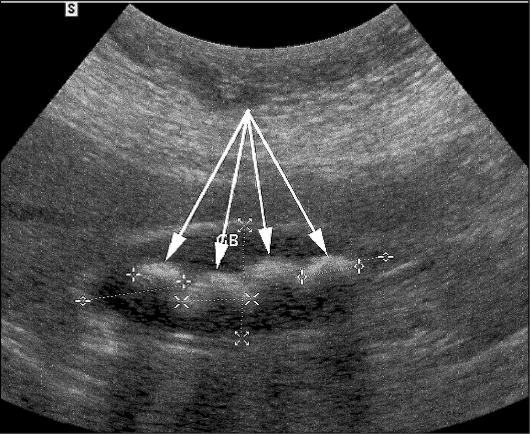

Кисты, заполненные серозной жидкостью, отображаются в виде округлых однородно анэхогенных (черных) зон, окруженных эхопозитивным (серого цвета) ободком капсулы с ровными четкими контурами. Специфическим эхографическим признаком кист служит эффект дорсального усиления: задняя стенка кисты и находящиеся за ней ткани выглядят более светлыми, чем на остальном протяжении (рис. 3.8).

Рис. 3.8. Эхографическое изображение солитарной кисты почки